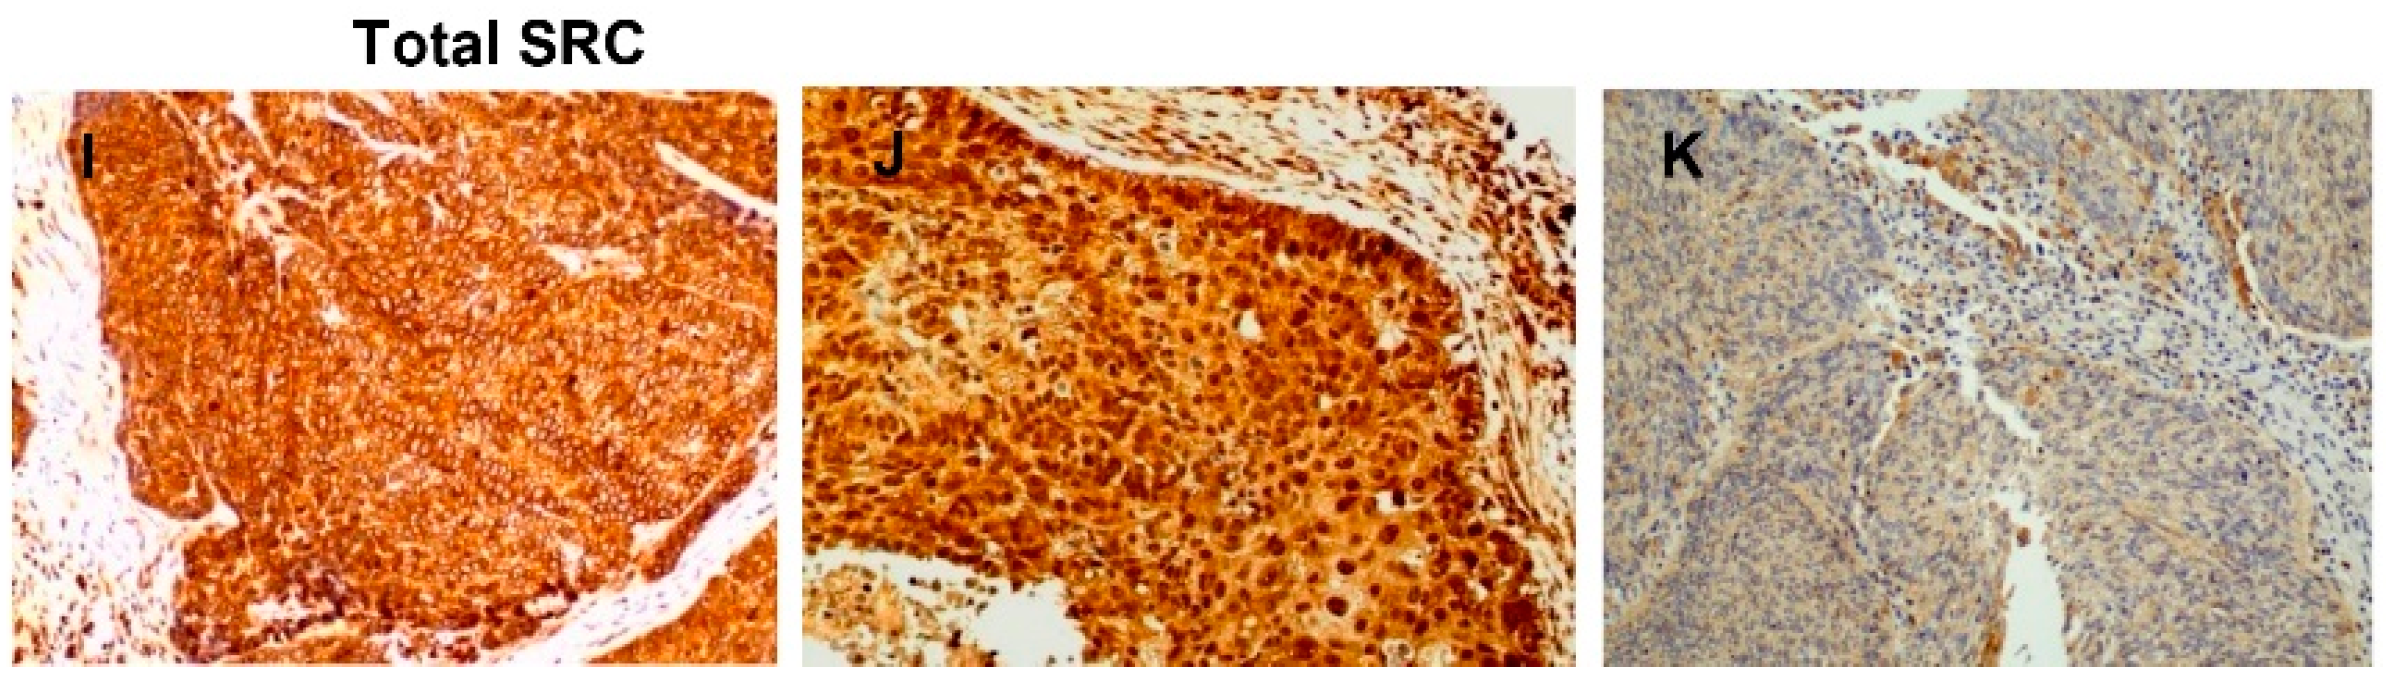

Immunohistochemical analysis of active SRC expression was performed on tissue specimens from 122 HNSCC patients. Immunostaining was successfully evaluated in 116 (95%) of the 122 cases. Of these 116 tumors, 88 (76%) exhibited positive SRC expression preferentially detected in the cytoplasm, although some cases also displayed protein enrichment at the cell membrane (Figure 1A–C). Normal epithelium showed positive staining in the basal cell layer and negligible expression in the most differentiated layers (Figure 1D). In addition, immunohistochemical analysis of p-SRC (Tyr419) and total SRC was also performed and correlated with active SRC expression (not phosphorylated at Tyr530). Positive p-SRC (Tyr419) staining was mainly detected in the nucleus in 98 (88%) of the tumors, and some cases also exhibited cytoplasmic staining (11 tumors) (Figure 1E–H). A significant positive correlation was observed between active SRC expression and nuclear p-SRC (Tyr419) (Spearman correlation coefficient 0.305, p = 0.001) but not cytoplasmic p-SRC (Tyr419) (Spearman correlation coefficient −0.023, p = 0.810). Concordantly, total SRC expression also exhibited both nuclear and cytoplasmic patterns (Figure 1I–K) and showed a significant correlation with active SRC expression (Spearman correlation coefficient 0.318, p = 0.001). The expression of p-SRC (Tyr419) was also confirmed by Western blot analysis in a subset of tumor samples compared to patient-matched normal tissues and in a panel of HNSCC-derived cell lines (Supplementary Materials Figure S1). Consistent with the IHC data, p-SRC (Tyr419) levels were increased in tumors compared to patient-matched normal epithelia (Patients 1–3) as well as HNSCC cells. Total SRC expression levels were also found to increase in tumors compared to the normal counterparts (Patients 1,2, and 4).

Figure 1. Immunohistochemical analysis of SRC expression in head and neck squamous cell carcinoma (HNSCC) tissue specimens. Representative examples of HNSCC showing positive active SRC staining (A,B, cytoplasmic and membrane enrichment), negative staining (C), and normal adjacent epithelia (D). Representative examples of tumors with positive p-SRC (Tyr419) staining (E, nuclear and F, cytoplasmic and nuclear), negative staining (G), and normal adjacent epithelia (H). Representative examples of tumors showing positive total SRC staining (I,J, cytoplasmic and nuclear) and negative staining (K). Magnification 20×. Scale bars = 50 μm.